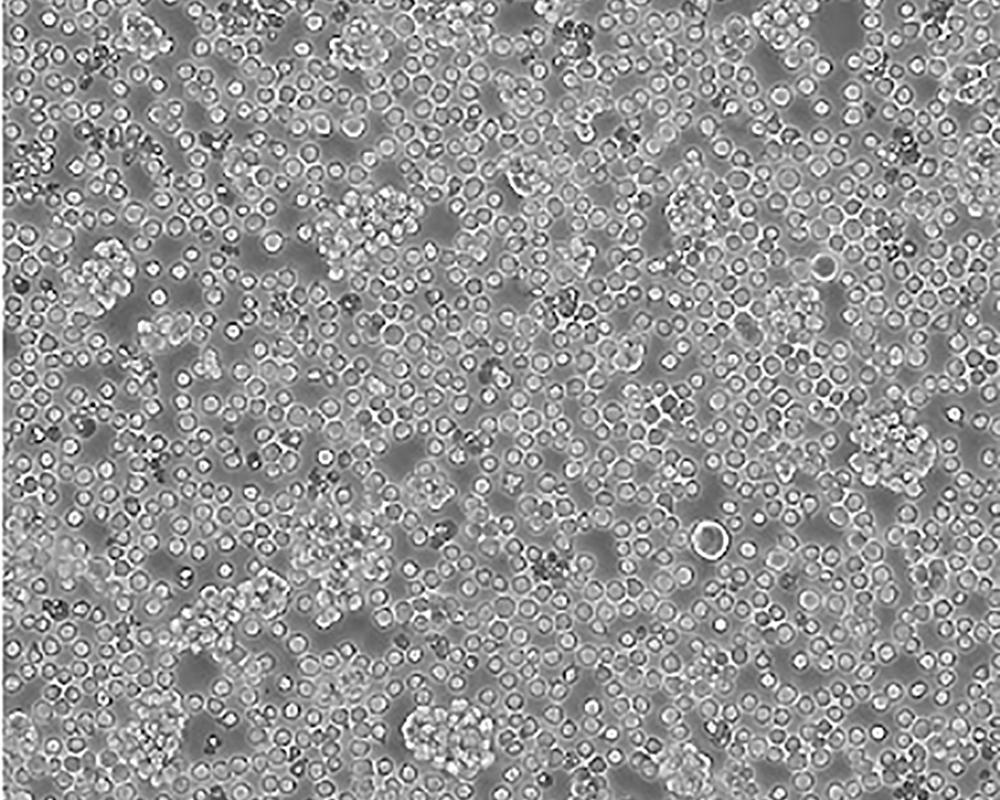

Jurkat, Clone E6-1 [Jurkat E6-1]

人T淋巴細胞白血病細胞

急性T淋巴細胞白血病;男性

Homo sapiens, human

suspension

lymphoblast

1:2-1:4

該細胞是Jurkat-FHCRC細胞株(Jurkat細胞株的衍生)的一個克隆。Jurkat細胞株來源于一個14歲男孩的外周血。經佛波酯和外源凝集素或抗T3單克隆抗體誘導后可產生大量IL-2(IL-2的產生需兩種類型的誘導劑);表達T細胞受體、CD3